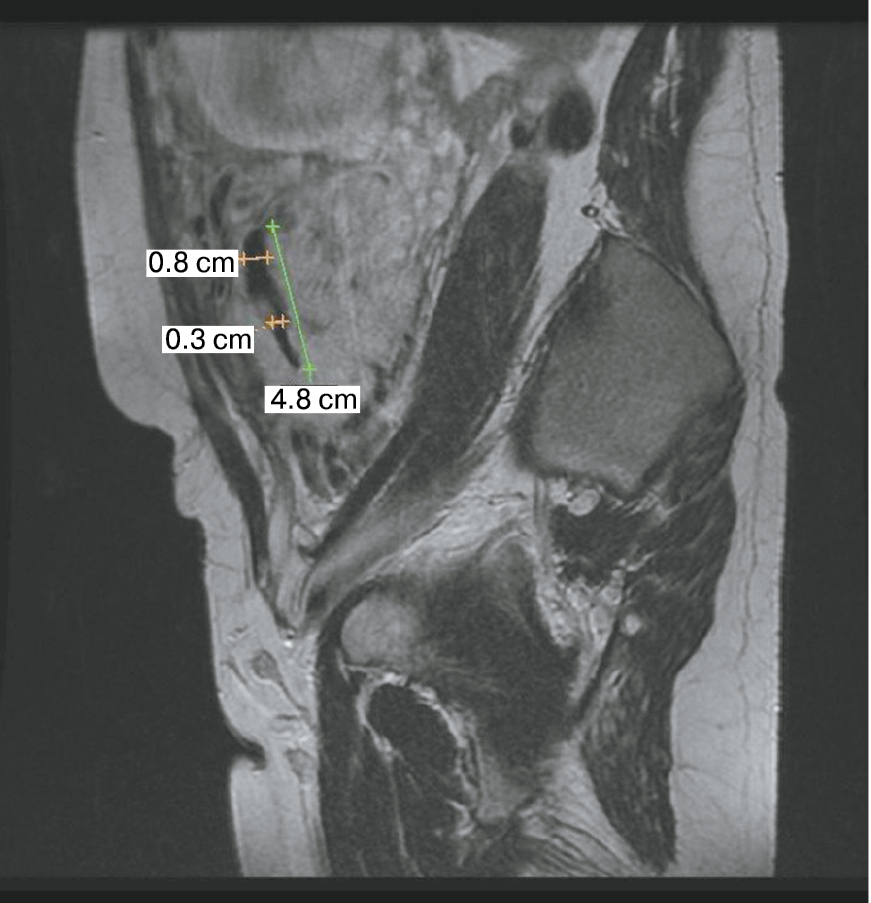

Также стоит выделить особый тип плацентарной гиперваскуляризации, а именно включение в плацентарной ткани изменений по типу «обнаженного сосуда» (рис. 1, 2). Мы провели анализ встречаемости данного признака среди наших пациентов. Любопытным наблюдением явилось то, что данный симптом в нашей выборке встречался только при наличии placenta percreta – 6 случаев, а именно при поражении параметриев, и не встречался при плацентарной инвазии, ограниченной миометрием. «Мостовидные сосуды» были менее специфичны, тем не менее, их наличие также сопровождало тяжелые формы врастания, обусловленные более глубокой инвазией ворсин хориона, – 8 случаев.

Рис. 1. МРТ placenta percreta, симптом «обнаженного сосуда»

Рис. 2. МРТ placenta percreta, симптом «обнаженного сосуда»

Является ли симптом «обнаженного сосуда» патогномоничным для параметральной инвазии или нет, еще предстоит выяснить; однако в ходе исследования установлена его связь с частотой гистерэктомий в группах с наличием симптома «обнаженного сосуда», что, вероятно, обусловлено мощной сосудистой сетью коллатералей и неоангиогенезом. Во всех случаях обнаружения данного признака впоследствии была выполнена вынужденная гистерэктомия (рис. 3–6, пациентка Н., 37 лет).

Рис. 5. Корональная проекция МРТ. 1 – интрамуральная гиперваскуляризация; 2- измененный контур мочевого пузыря

Рис. 6. Корональная проекция МРТ. 1 – обнаженный сосуд; 2 – интрамуральная гиперваскуляризация; 3 – гиперваскуляризация плаценты